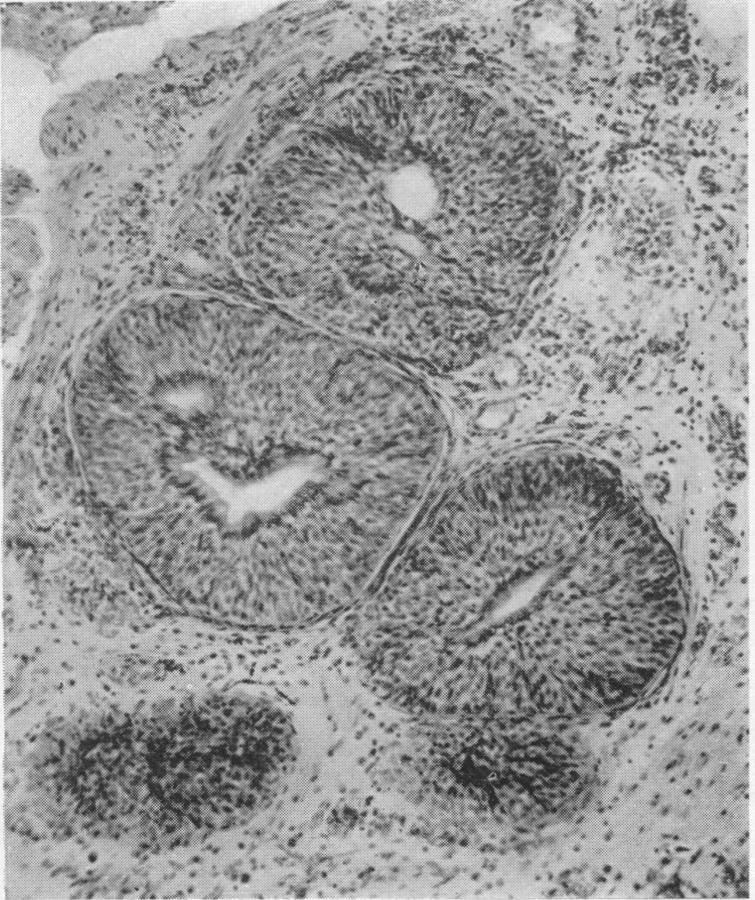

THE POTENTIAL MALIGNANCY IN EXSTROPHY OF THE BLADDER.

Ann Surg. 1922 Mar;75(3):365-71. doi: 10.1097/00000658-192203000-00008.